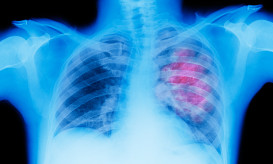

Ο προσυμπτωματικός έλεγχος για τον πνεύμονα γίνεται με αξονική τομογραφία θώρακος χαμηλής δόσης.